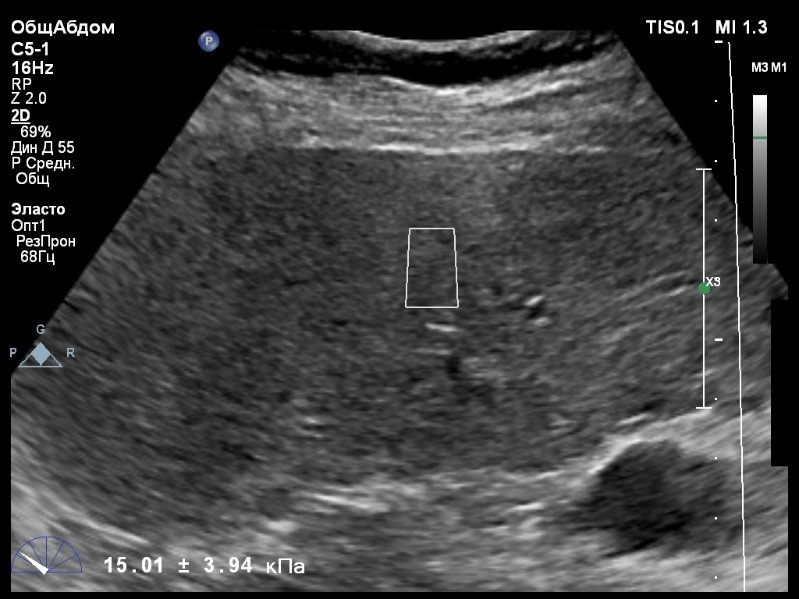

Предыдущее исследование было выполнено с помощью транзиентной эластографии, получена медиана жесткости 16,9 кРа (13,8-22,8). На момент настоящего исследования, пациент не принимал пищу на протяжении 4 часов, АСТ, АЛТ не превышают патологических значений.

Пациент обратился к доктору с направлением на исследование степени жесткости печени.

В виду технических сложностей выполнения исследования (избыточная масса тела), для оценки жесткости была выбрана технология компании Philips ElastPQ (точечная эластография) и прибор компании Philips Epiq 7. Исследование было проведено в соответствии с клиническими рекомендациями для ультразвуковых приборов компании Philips. В результате исследования были получены следующие результаты:

| 1 [16.86] kPa | 2 [15.14] kPa | 3 [12.83] kPa |

| 4 [12.81] kPa | 5 [13.07] kPa | 6 [15.01] kPa |

| 7 [16.95] kPa | 8 [14.06] kPa | |

Стандартное Отклонение [1.62] kPa Медиана Жесткости [14.54] kPa Фактор Качества IQR/Med 12%

Зона интереса расположена на более чем на один сантиметр глубже капсулы, параллельно ходу луча, в середине изображения, в участке печени лишенном артефактов

Капсула видна как яркая белая линия перпендикулярная ходу ультразвукового луча.

Стандартное отклонение (3,94 kPA) не превышает 30 процентов от полученного значения (15,01 kPA).

Для интерпретации полученных клинических данных были использованы Рекомендации по проведению эластографии сдвиговой волной для оценки жесткости печени при использовании ультразвуковых аппаратов компании Филипс с примером протокола. Стоит отметить, что для проведения исследования у технически сложного пациента был выбран аппарат экспертного класса. Подготовка пациента соответствовала проводимому исследованию. Представленные слайды проведенного исследования свидетельствуют о правильном техническом исполнении проб, что позволяет заключиться о достоверности полученных измерений. Таким образом, учитывая полученную медиану жесткости на уровне 14,54 кРа (12.83-16.95 kPa) и уровень стандартных отклонений не превышающих 30%, полагаю, что уровень степени фиброза соответствует стадии F4. Заведующий отделением УЗД МЦ «Асклепий», Глушенко Д. Е.